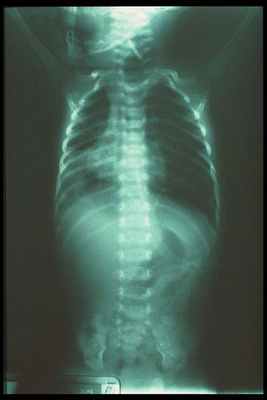

Если пробы с желудочным зондом подтвердили наличие атрезии, ребёнка переводят в хирургический стационар и делают рентгенологическое обследование.

На обследовании выполняются рентгеновские снимки грудной клетки и брюшной полости, предварительно в пищевод устанавливают рентген-контрастный зонд. Исследование проводится в прямой проекции в вертикальном положении ребёнка. Оценивают уровень стояния зонда (свёрнутый зонд в слепом верхнем сегменте); газонаполнение желудка и кишечника (при наличии трахео-пищеводного свища между нижним сегментом и трахеей будет определяться воздух в брюшной полости, при отсутствии воздуха в желудке и кишечнике исключается наличие нижнего трахеопищеводного свища).

Во время проведения рентгенологического обследования можно выявить сопутствующие патологии — непроходимость кишечника, пороки развития позвоночника и пневмонию.